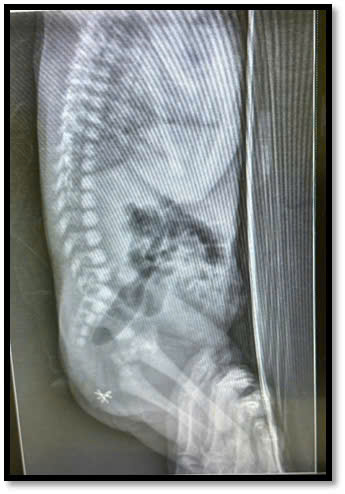

Ngay sau sinh tháng 3/2025, bé trai T.K.N. được bác sĩ sơ sinh phát hiện ARM thể “không có đường rò”, đây là thể bệnh tương đối hiếm. Bệnh nhi còn có tinh hoàn ẩn, nằm trong hội chứng VACTERL. Chỉ vài giờ sau chào đời, bé được mổ cấp cứu mở hậu môn tạm ra da để giải áp, cứu sống và tạo điều kiện phát triển thể trạng trước những cuộc phẫu thuật phức tạp tiếp theo.

Tháng 7/2025, sau hơn 3 tháng đồng hành cùng hậu môn tạm, bé đủ sức khỏe để bước vào ca mổ tái tạo hậu môn “thật” bằng kỹ thuật PSARP. Ekip phẫu thuật đã bóc tách bóng trực tràng, tạo hình hậu môn mới và bắt đầu lộ trình nong hậu môn đều đặn để phòng ngừa biến chứng hẹp.